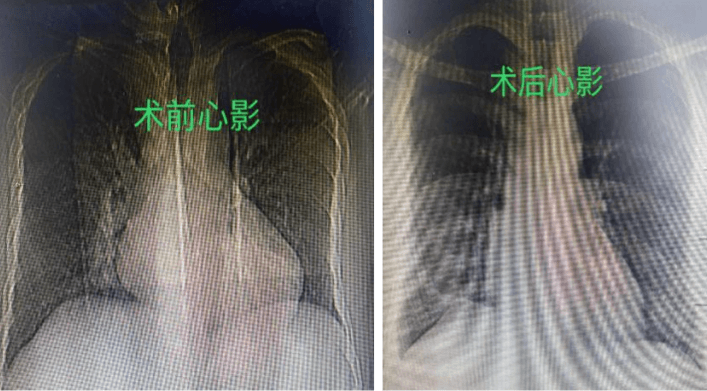

7月25日,在麻醉團隊、體外循環(huán)等團隊的保駕護航下,祝恒山主任帶領(lǐng)的手術(shù)團隊在張先生的右側(cè)腋下切口了一個不到5厘米的小切口,開始為患者實施二尖瓣成形術(shù)和房間隔缺損修補術(shù),不到3個小時,手術(shù)團隊便順利地為患者的心臟進行了“修補”,術(shù)后復(fù)查胸片及心臟超聲效果滿意。